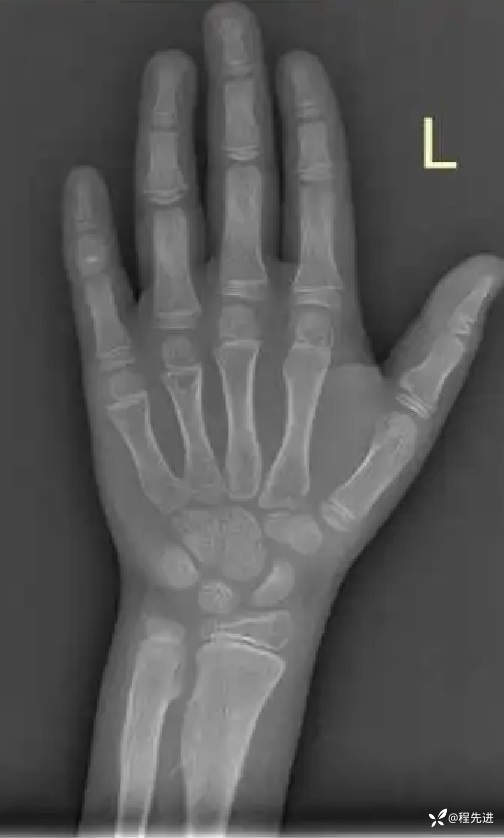

左腕关节DR: